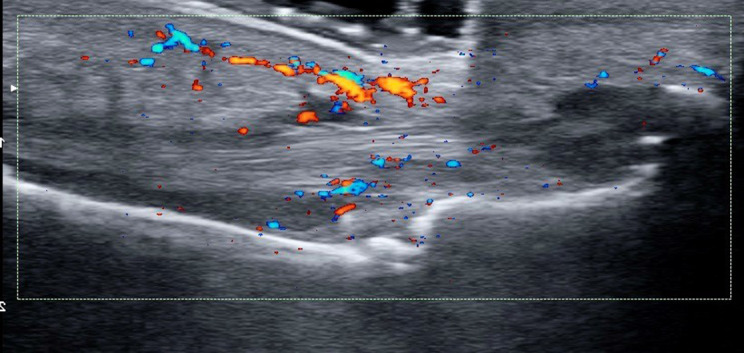

Dactylitis is a clinical concept that corresponds to the swelling of the whole finger or toe giving a sausage appearance. Although it can be observed in different diseases, it is a distinctive clinical feature of psoriatic arthritis and is associated with a poor prognosis. Ultrasound has made it possible to improve our understanding of the pathogenesis of psoriatic arthritis dactylitis, identifying associated structural alterations, namely, flexor tenosynovitis, subcutaneous tissue edema, pulley inflammation with thickening and intra-pulley Doppler signals, extensor paratenonitis, synovitis, pericapsular bone formation, and flexor enthesitis. Given its complexity, a consensus has yet to be reached on an ultrasound-based definition of dactylitis. In addition, enthesitis is one of the characteristic features of spondyloartritis. Enthesitis, like dactylitis, is among the clinical manifestations in the Assessment of SpondyloArthritis international Society classification criteria for both axial and peripheral spondyloartritis and is a key feature for classifying psoriatic arthritis with the Classification criteria for Psoriatic Arthritis criteria. Ultrasonography is a very useful tool for exploring the enthesis. We have a good sonographic definition, although ultrasound findings do not always allow us to differentiate between mechanical or inflammatory lesions. Elementary lesions that characterize enthesopathy are hypoechogenicity at the enthesis, thickened enthesis, calcification/enthesophyte at enthesis, erosion at enthesis, and Doppler signal at enthesis. Different composite indices have been proposed in order to classify spond yloarthropathies. This article reviews the evaluation of dactylitis and enthesitis from the sonographic perspective.